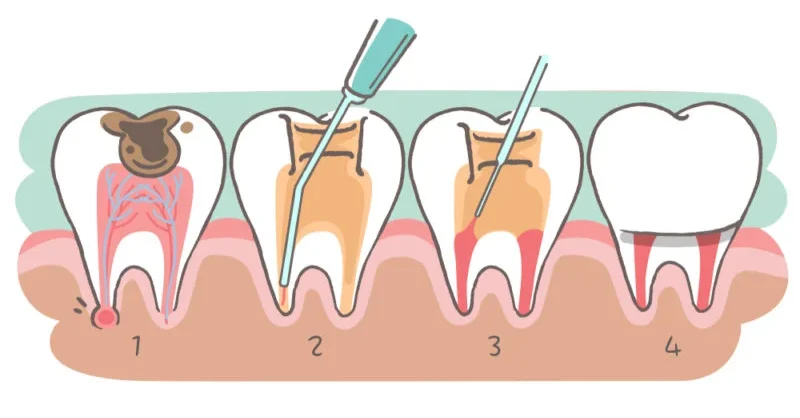

Save Your Natural Tooth with Expert Root Canal Treatment

Root canal therapy is a crucial procedure for saving teeth that are severely infected or damaged. At Vitalis Dental, our experienced endodontists perform precise root canal treatments to eliminate infection and restore your tooth’s functionality.

A root canal procedure involves removing the infected or damaged pulp from the tooth, cleaning and disinfecting the interior, and then sealing it. The process typically involves local anesthesia to ensure comfort. After the procedure, a crown or filling is placed to restore the tooth’s functionality and appearance.